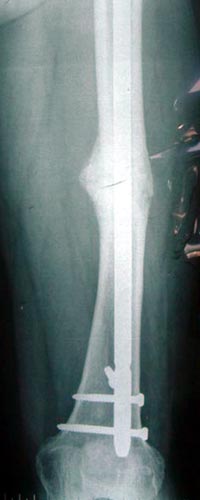

病例一、患者22岁,股骨中下1/3骨折骨不连2年,明显畸形。

X线片显示钢板螺钉已经松脱,固定失败,断端骨折端硬化

我们用髓内钉内固定后保证早期稳定性,植骨补充成骨所需基质,骨生长因子和骨髓细胞的植入,可分化成为骨痂组织,有效促进了骨不连的愈合